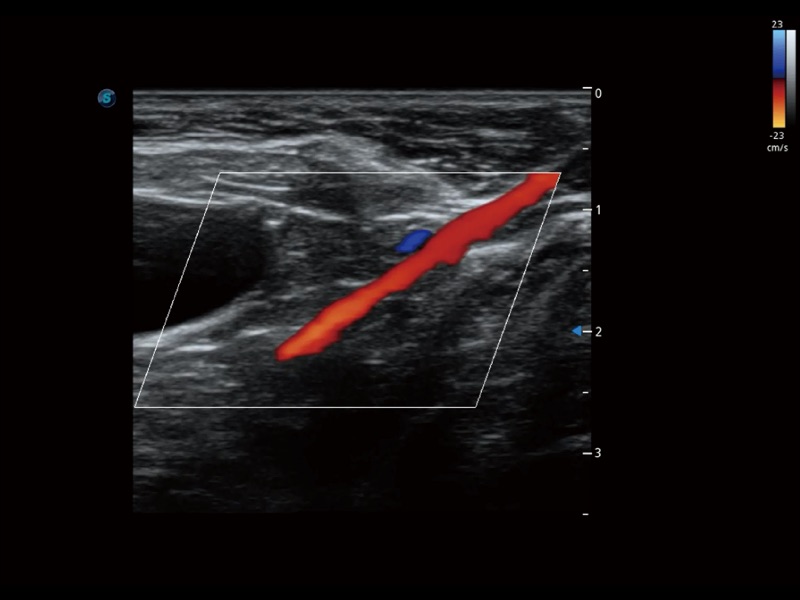

(犬)髂动脉血流